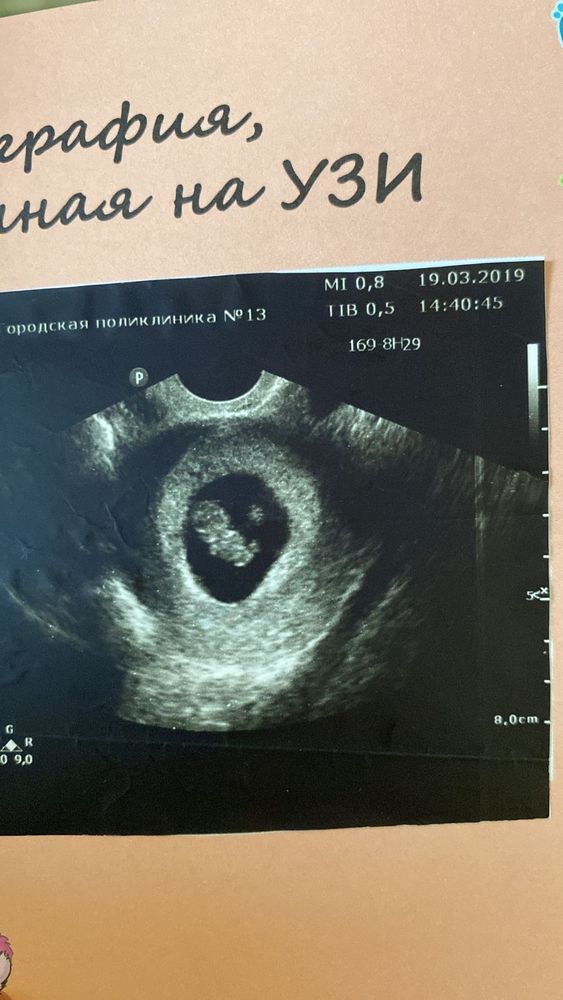

Это ровно в 7 недель